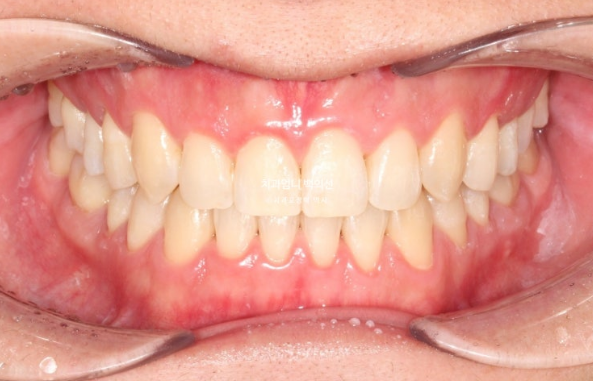

In the front teeth area, once the open bite and reverse bite were corrected, a stable bite was created.

Even after palatal expansion, the buccal corridor does not necessarily disappear.

The asymmetry of the chin appears to have been reduced compared with the beginning.

Clean front tooth angulation